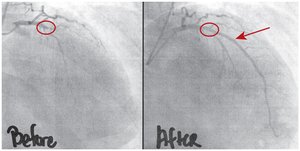

Stent Placement and Angioplasty

Stents and balloon angioplasty are used to treat blocked arteries:

Stent: Mesh tube placed to keep artery open.

Balloon angioplasty: Balloon compresses plaque against artery wall.